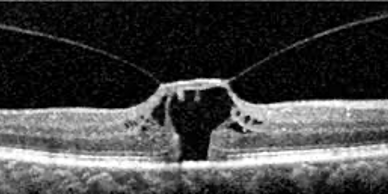

A telangiectasia macular é uma anormalidade dos capilares foveais e perifoveais associada à perda das camadas nucleares externas e da zona elipsoide, podendo progredir para lesões císticas (cavitações).